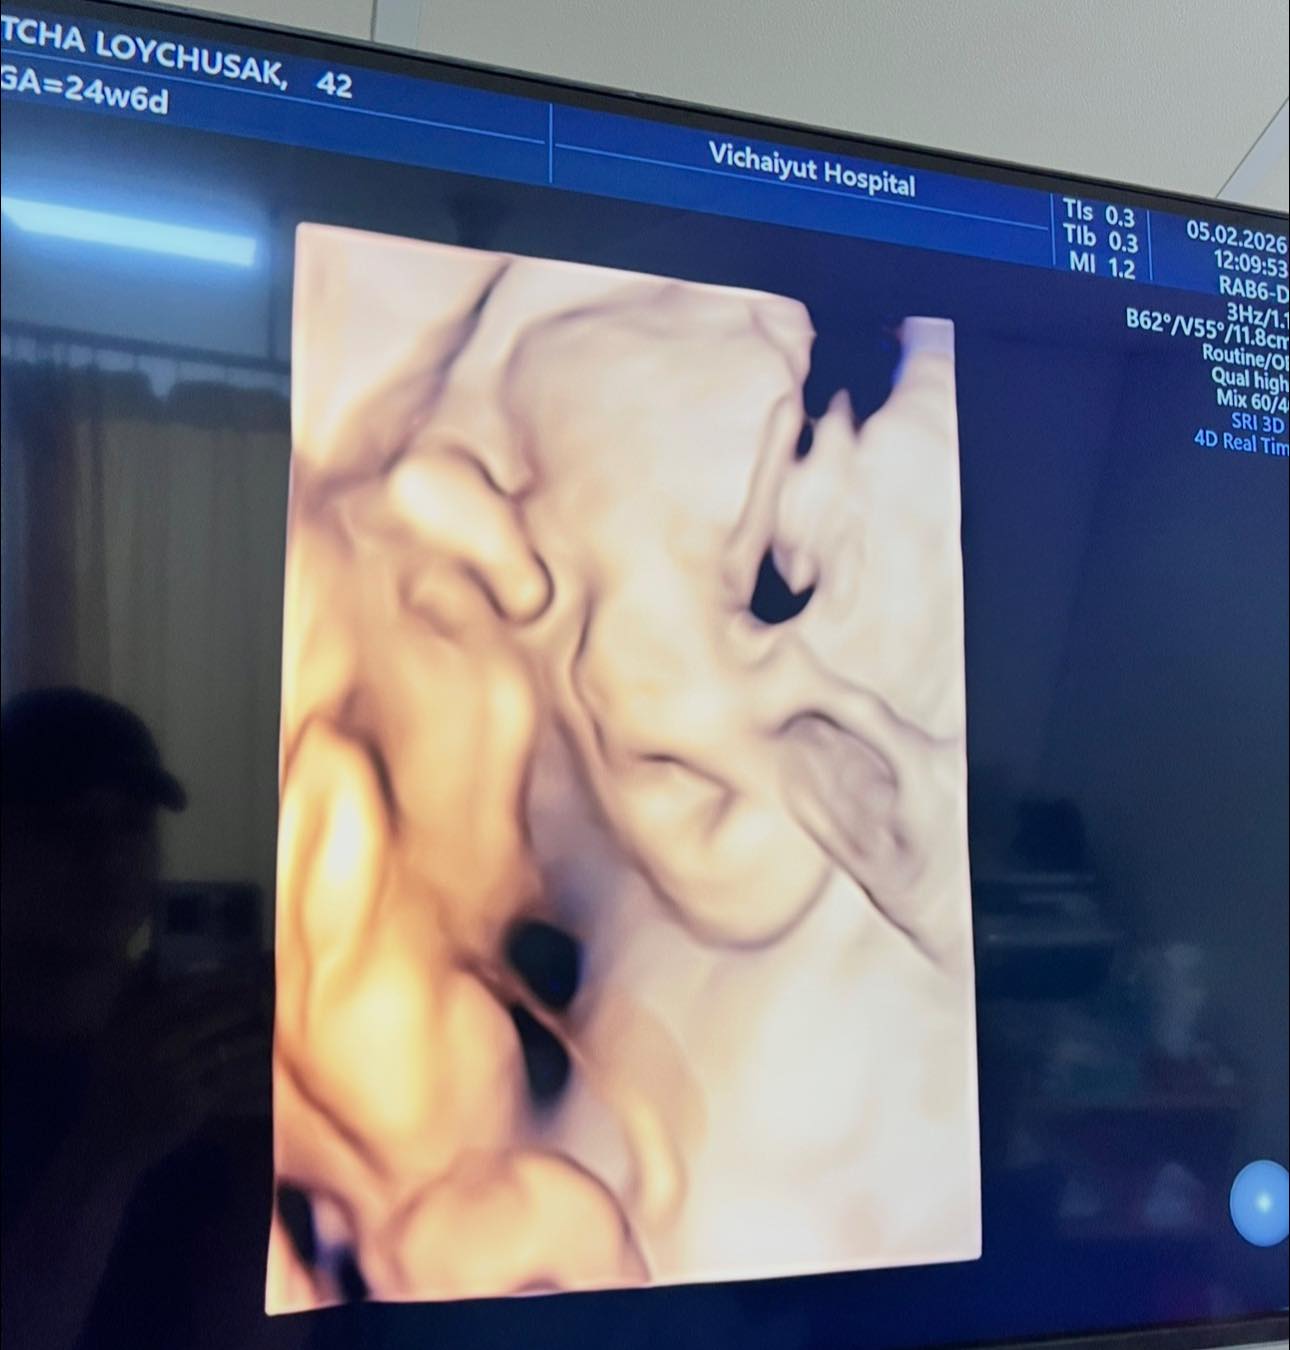

ทำเอาแฟน ๆ เตรียมสมัครเป็นพี่เลี้ยงออนไลน์กันล่วงหน้า เมื่อ เจมส์ เรืองศักดิ์ ลอยชูศักดิ์ ออกมาแชร์โมเมนต์อบอุ่น อัปเดตการตั้งครรภ์ของภรรยาคนสวย ครูก้อย นัชชา ลอยชูศักดิ์ พร้อมเผยภาพอัลตราซาวด์ของลูกสาวคนที่ 2 “น้องมีเมตตา” ที่ตอนนี้อายุครรภ์ครบ 6 เดือนแล้ว

จากภาพอัลตราซาวด์เผยให้เห็นเค้าโครงใบหน้าของน้องมีเมตตาอย่างชัดเจน นอนยิ้มหวานละมุน แถมจมูกโด่งสะดุดตา เรียกได้ว่าน่ารักน่าชังตั้งแต่อยู่ในท้อง โดยพ่อเจมส์เขียนแคปชันด้วยความเอ็นดูว่า “แม่หนูมีเมตตาของฉัน จมูกโด่ง ยิ้มหวาน” พร้อมอัปเดตว่า คุณหมอกล้วย แพทย์ผู้ดูแลครรภ์ครูก้อย ยืนยันว่าลูกน้อยแข็งแรงสมบูรณ์ พัฒนาการเป็นไปตามเกณฑ์ทุกด้าน ก่อนจะปิดท้ายด้วยมุกขำ ๆ สไตล์คุณพ่อว่า “สินค้าเด็กเข้าได้เลยครับ ( ฮาาา.... )” ทำเอาแฟน ๆ เข้ามากดไลก์และคอมเมนต์ชื่นชมความน่ารักของน้องมีเมตตาอย่างล้นหลาม

ด้านคุณแม่คนสวย ครูก้อย นัชชา ก็ไม่น้อยหน้า โพสต์คลิปอัลตราซาวด์ของลูกสาวเช่นกัน พร้อมแคปชันสั้น ๆ ว่า “แม่ว่า…ดูทรงยาว ทรงคมนะ” งานนี้หลายคนอดเดาไม่ได้ว่า น้องมีเมตตาน่าจะได้ความสูงยาวและเค้าโครงคม ๆ มาจากพ่อเจมส์และแม่ก้อยแบบเต็ม ๆ

ก่อนหน้านี้ ครูก้อยเคยให้สัมภาษณ์ว่า การตั้งครรภ์ครั้งนี้แพ้ท้องน้อยมาก อารมณ์ดี มีความสุขตลอด เนื่องจากมีการเตรียมความพร้อมอย่างรอบด้านตั้งแต่ก่อนตั้งครรภ์ ทั้งการจัดการเรื่องงาน โภชนาการ และการออกกำลังกาย เนื่องจากมีภาวะมีบุตรยากจึงมีความเตรียมความพร้อมเป็นพิเศษ เมื่อทุกอย่างลงตัวก็ส่งผลให้ลูกน้อยในท้องอารมณ์ดีตามไปด้วย จนเห็นได้จากภาพอัลตราซาวด์ที่น้องมีเมตตานอนยิ้มหวาน น่าเอ็นดูตั้งแต่อยู่ในท้อง